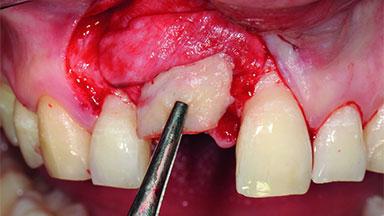

Replacement of a Compromised Upper Right Central Incisor: Hard- and Soft-tissue Augmentation, Late Placement of an RC Bone Level Implant

A 36-year-old male patient with a compromised maxillary central incisor was referred by his general dentist for consultation. The patient’s chief complaints were the gradual debonding of a temporary crown on the right central incisor and unsatisfactory esthetics due to an increasing diastema between the right central and lateral incisors. The patient reported a traumatic event some years previously, when a crown had been placed after root-canal treatment. The referring dentist wanted to provide a new crown restoration, but was concerned about the condition of the residual root. Anamnesis was negative for any other dental or periodontal pathology in the remaining dentition. The patient reported taking no medications: He was a smoker (10 to 15 cigs/day) and had realistic esthetic expectations.

Bone Augmentation Horizontal|Simultaneous|Staged

Augmentation Materials Xenogenous|Membrane

Soft Tissue Grafting Simultaneous